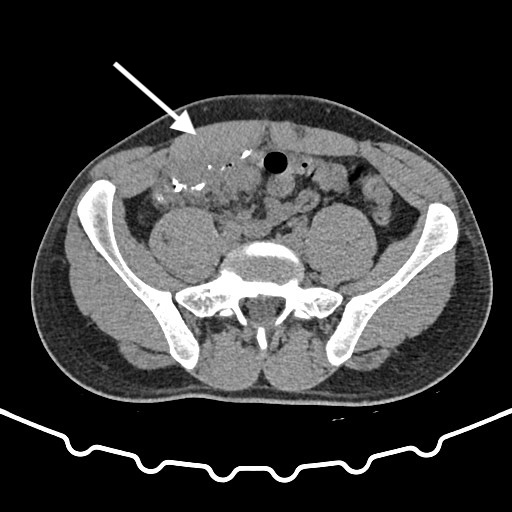

Three years after the appendectomy, the patient returned to the emergency department due to periumbilical pain and erythema that had persisted for three months. On further questioning the patient also reported intermittent diarrhea for one week, with no accompanying vomit or fever. During the physical examination, erythema and pain upon palpation of the umbilicus were observed. The blood tests showed no significant changes. Imaging with a CT scan and fistulogram through the umbilical granuloma allowed for the identification of a fistulous tract to a pericecal collection (figure 1-3). The patient was admitted and started on empiric antibiotic therapy with piperacillin and tazobactam.

Fig. 1-2: CT scan with fistulogram through the umbilical granuloma showing the fistulous tract to the cecum (white arrow) - axial view.